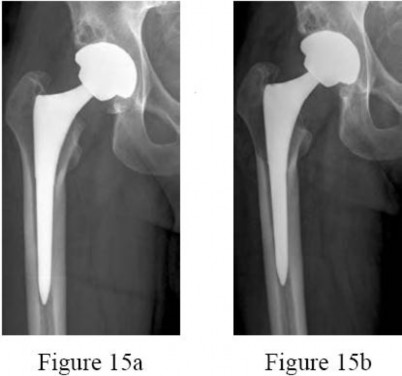

Figures 15a and 15b are the 6-week postsurgical anteroposterior hip radiograph and current radiograph of a 54-year-old avid hiker who returns for routine follow-up 3 years after an uncomplicated uncemented modular metal-on-metal hip replacement. He reports mild activity-related aching diffusely around the right hip region, but does not feel restricted with his activities. Examination reveals no local tenderness, a well-healed incision, and mild discomfort at the extremes of rotation. An erythrocyte sedimentation rate (ESR) and C-reactive protein (CRP) are obtained, showing 9 mm/h (reference range, 0-20 mm/h) and 2.0 mg/L (reference range, 0.08-3.1 mg/L), respectively. What is the etiology of the radiographic finding?

---

The radiograph shows a large area of osteolysis involving the proximal femur. The implants appear solidly fixed on radiographs and, in the absence of symptoms, it is unlikely the implants are loose or infected. Although infection or metastatic disease is a possibility, the normal ESR and CRP values make the diagnosis of deep infection unlikely. The most likely cause for the radiographic findings is wear from metal particles resulting in an adverse local tissue response and osteolysis.